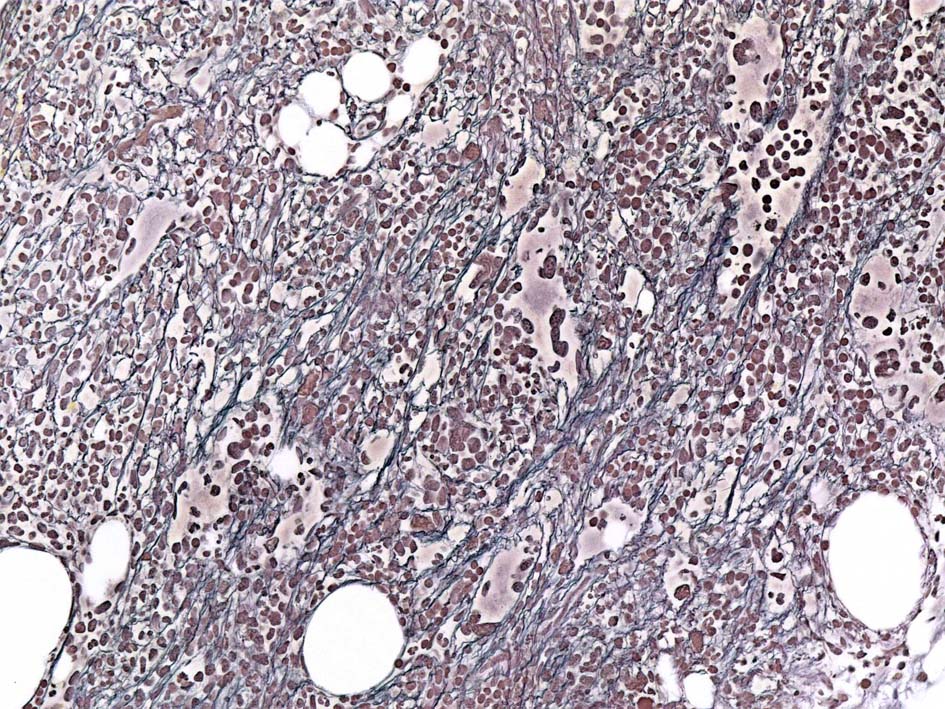

塗銀染色

黒染する弾性線維の増生のほか, 赤く染まる膠原線維の増生が確認される. MF-2 fibrosis. 鍍銀染色の核染色をすると膠原線維の赤染がわからなくなるので行わない.